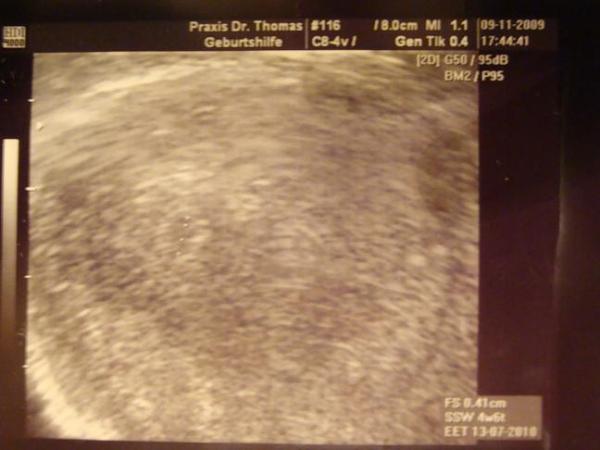

nach dem hier einige schon was zu sehen hatten auf ihren us hab ich etwas angst das was nicht in ordnung ist , ich bin so ängslich in der ss das ist schon schlimm . ich häng euch mal ein bild ran

Bild zu etwas angst - Forum für Juli - Mamis